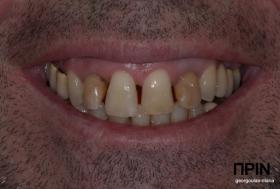

ΠΡΟΣΘΕΤΙΚΗ ΑΠΟΚΑΤΑΣΤΑΣΗ ΣΤΗΝ ΑΝΩ Κ ΚΑΤΩ ΓΝΑΘΟ ΚΑΙ ΤΟΠΟΘΕΤΗΣΗ ΕΜΦΥΤΕΥΜΑΤΩΝ ΜΕ ΚΛΕΙΣΤΗ ΑΝΥΨΩΣΗ ΙΓΜΟΡΕΙΟΥ

Ο ασθενής  προσήλθε στο ιατρείο μας θέλοντας να βελτιώσει την εμφάνιση των πρόσθιων δοντιών του και να αποκαταστήσει την υγεία κ την λειτουργία όλου του στόματος. Πραγματοποιήθηκε περιοδοντική θεραπεία κ ενδοδοντικές θεραπείες (απονευρώσεις) όπου κρίθηκε απαραίτητο και στη συνέχεια τοποθετήθηκαν 3 εμφυτεύματα, 2 δεξιά στις θέσεις του πρώτου κ δεύτερου γομφίου κ 1 αριστερά στη θέση του πρώτου προγομφίου. Κατά την  τοποθέτηση των 2 εμφυτευμάτων της δεξιάς πλευράς, πραγματοποιήθηκε κλειστή ανύψωση ιγμορείου με το σύστημα Piezotome-Intralift , τεχνική που εξασφαλίζει τη μικρότερη δυνατή επέμβαση κ τη μικρότερη μετεγχειρητική ταλαιπωρία (minimally invasive), καθώς κ αυξητικους παράγοντες PRF. Σε όλη τη διάρκεια της θεραπείας  ο ασθενής ήταν καλυμμένος τόσο αισθητικά όσο και λειτουργικά με προσωρινές μεταβατικές αποκαταστάσεις. 4 μήνες μετά την  τοποθέτηση των εμφυτευμάτων κ την οστεοενσωμάτωσή τους, ακολούθησε η τοποθέτηση των μόνιμων αποκαταστάσεων.